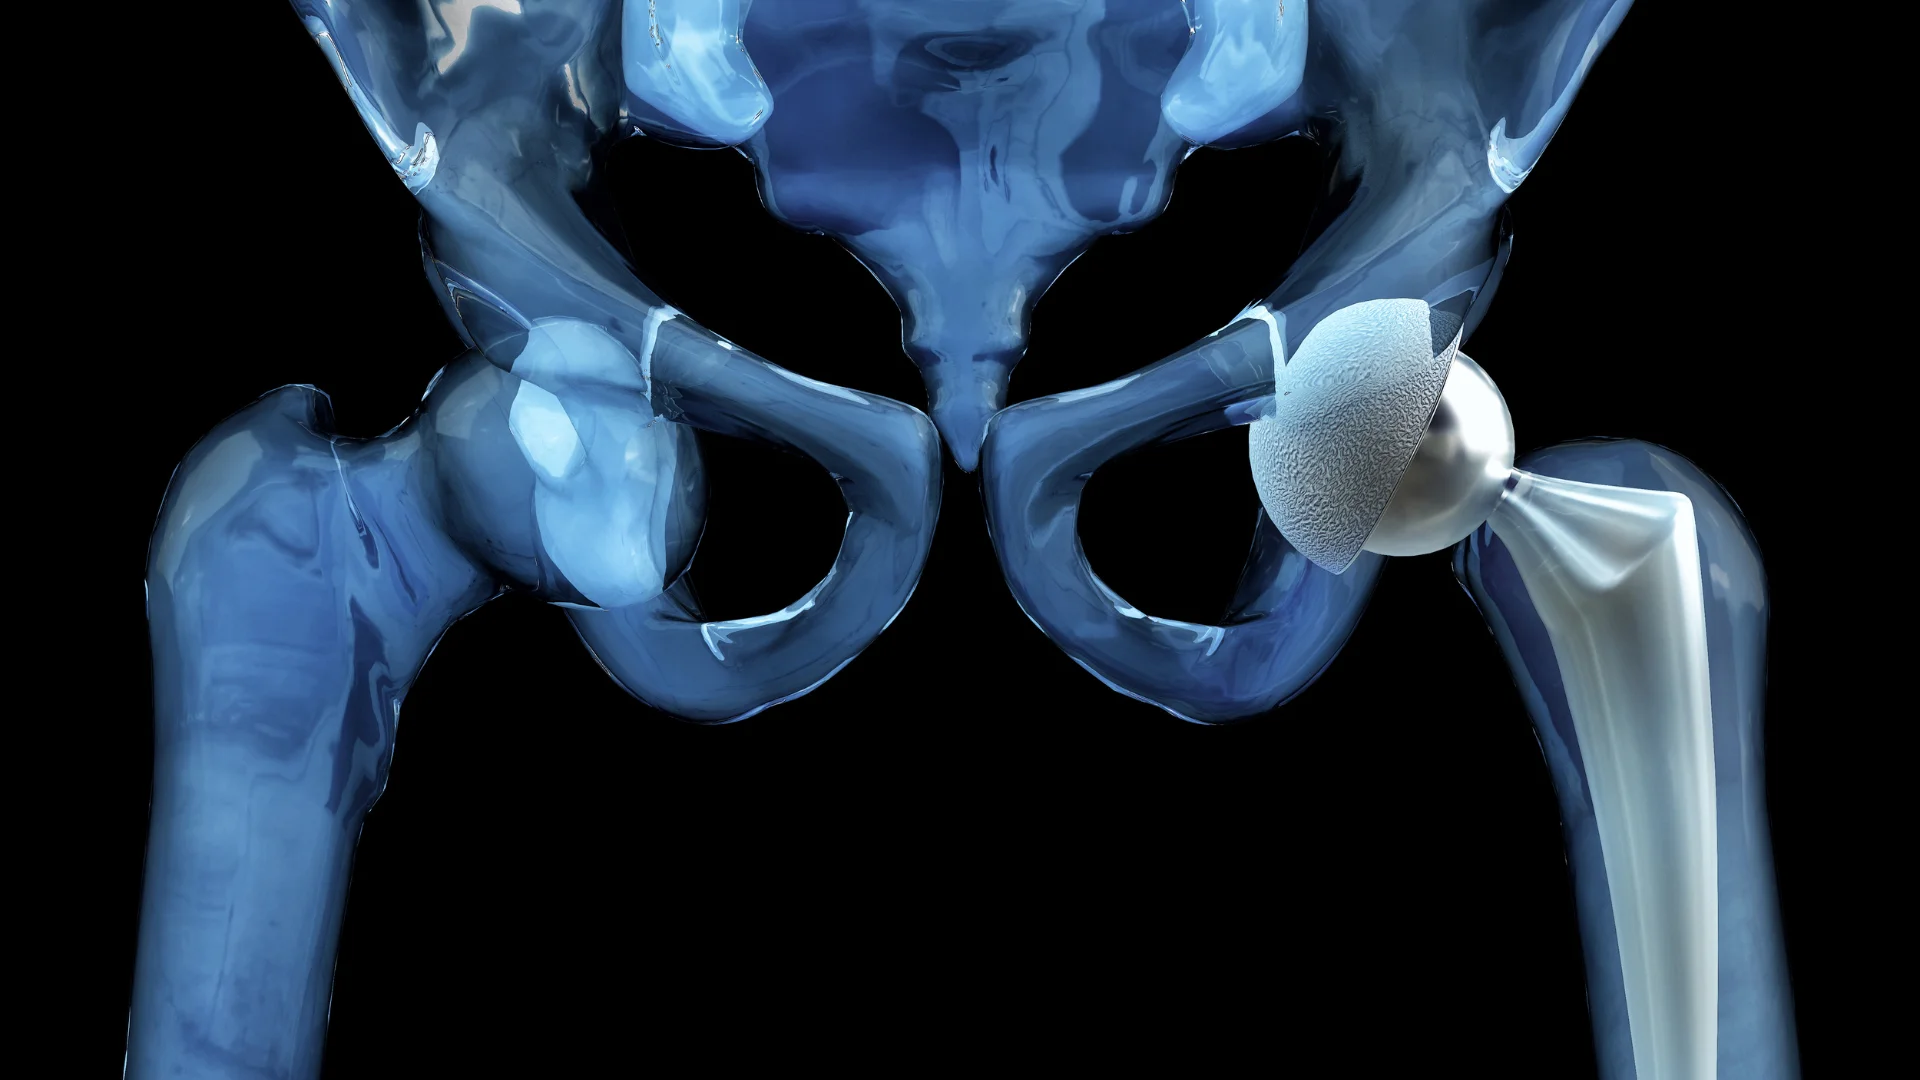

Ендопротезування повертає якість життя, знімає біль і дає можливість рухатися без обмежень. Але жоден імплант не є абсолютно вічним, термін його служби залежить від матеріалів, техніки встановлення і того, як пацієнт поводиться після операції. Розуміння цих факторів допомагає зберегти протез у робочому стані на багато років.

Більшість якісних імплантів працюють 15-20 років, а деякі й довше - понад два десятиліття. Керамічні та поліетиленові пари тертя мають кращу зносостійкість, а сучасні фіксаційні технології додатково підвищують стабільність. У молодих і фізично активних людей протез може зношуватися швидше, тоді як у старших темп зношування повільніший.

Ендопротез починає працювати одразу після встановлення, але інтенсивність навантажень має зростати поступово. Різкі рухи, надмірна вага та травми можуть прискорити зношування. Водночас правильний режим дозволяє імпланту служити дуже довго.